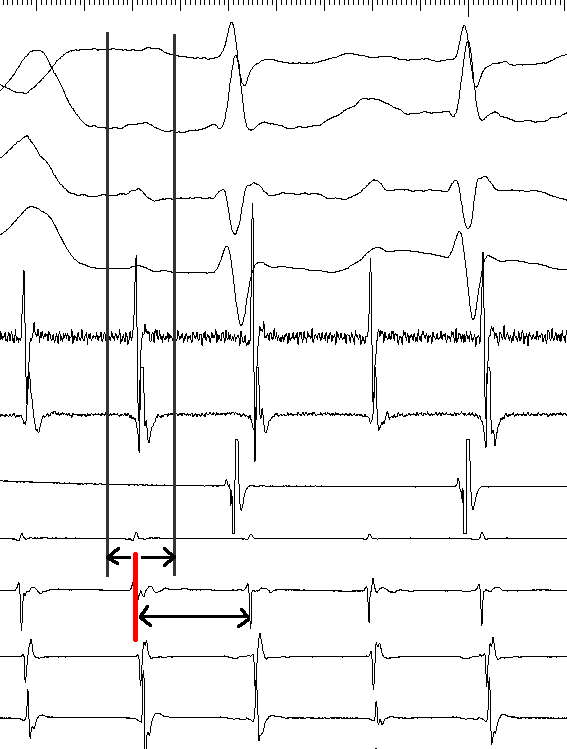

entrainment_three_sites.png

Miyazaki H, Stevenson WG, Stephenson K, Soejima K, Epstein LM. Entrainment mapping for rapid distinction of left and right atrial tachycardias. Heart Rhythm. 2006 May;3(5):516-23. doi: 10.1016/j.hrthm.2006.01.014. Epub 2006 Feb 28. PMID: 16648054.